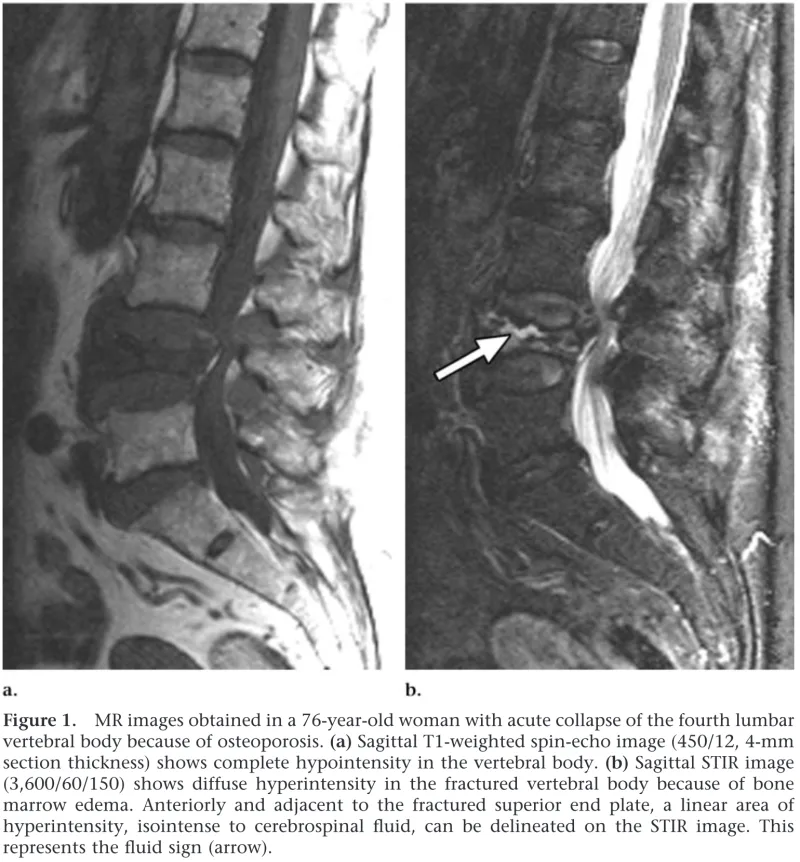

T1強調画像(a)では, 椎体が全体に灰色に変色しています.

一方, STIR像(b)では, 椎体の中に真っ白く写る部分があります.

これは椎体骨折後に骨が血液循環不良に陥って死んでしまう壊死(えし)を生じた所が空洞となり, そこに体液が貯まった所見です.

この所見を, fluid signといいます.

撮像されたMRIでは, 以前骨折した第2腰椎の一部が血液循環不良によって死んでしまう壊死(えし)を生じた後, 空洞を形成して, そこに体液が貯まったfluid signを認めました. さらに同じ椎体に再骨折を生じた所見も認めました. 第2腰椎椎体骨折後の再骨折と診断しました.